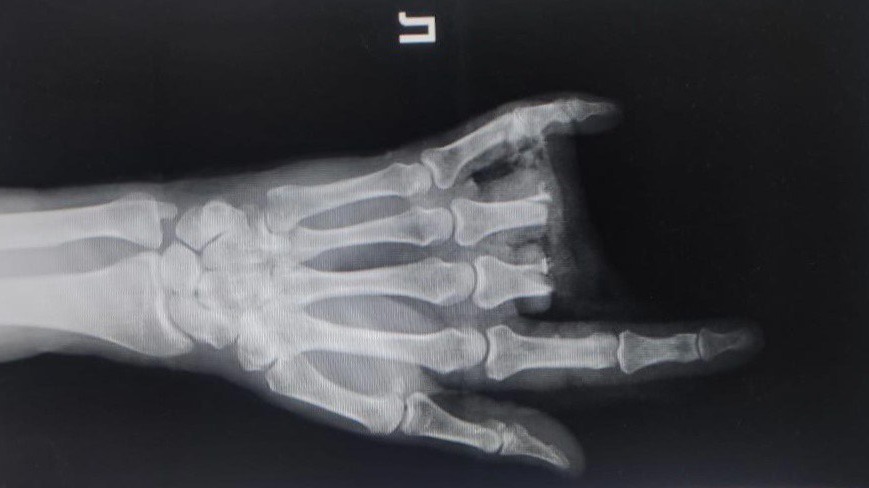

Житель Подмосковья отрезал себе два пальца болгаркой

Фото: Пресс-служба Министерства здравоохранения Московской области

В Подмосковье врачи пришили мужчине пальцы, которые он отпилил себе болгаркой. Об этом сообщили в пресс-службе Минздрава Московской области в среду, 10 мая.

По данным ведомства, инцидент произошел в Кашире. 56-летний местный житель работал болгаркой и отрезал себе средний и безымянный пальцы. Собрав их в банку, мужчина вызвал скорую помощь. Пострадавшего госпитализировали в травматологическое отделение местной больницы.

— После хирургической обработки ран мы зафиксировали пальцы в функционально выгодном положении при помощи спиц. Затем восстановили сосуды, сшили вены, артерии, тем самым восстановили функции конечности, — рассказал о произошедшем заведующий отделением Константин Смирнов.

Операция длилась два с половиной часа и завершилась успешно. Подвижность пальцев мужчине сохранили, он уже чувствует себя лучше. После прохождения реабилитации пациент будет выписан.